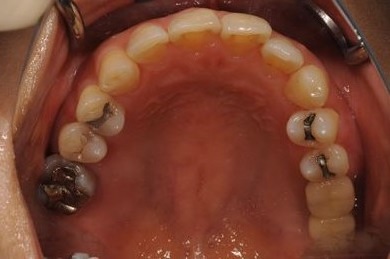

インプラントの症例写真 IMPLANT

骨再生インプラント治療+セラミック治療+歯肉歯槽骨整形

| 性別/年齢 | 女性 / 42歳 | ||||||||||||||||||||||||||||||||

| 主訴 | インプラント治療を受けたい。 | ||||||||||||||||||||||||||||||||

| 治療方針 | 左上奥欠損部分をインプラント治療にて機能的・審美的回復を行う。 | ||||||||||||||||||||||||||||||||

| 治療内容 | インプラント2本(ソケットリフト)、メタルボンドセラミック3本(メタルボンド用土台1本)、歯肉歯槽骨整形 | ||||||||||||||||||||||||||||||||

| 総治療費 | 1,227,713円 | ||||||||||||||||||||||||||||||||

| 治療期間 | 11ヶ月 |